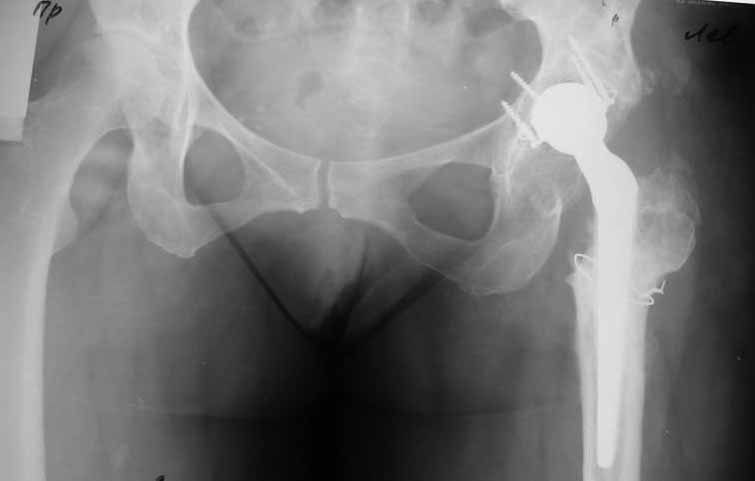

Уважаемые коллеги. Хотелось бы услышать мнения и советы по представляемому случаю. Пациентка 45 лет. Бесцементное эндопротезирование левого тазобедренного сустава 6 лет назад (впадина RM, Mathys, металл-металл, ножка Зульцеровская). За 10 лет до протезирования – коррегирующая остеотомия бедренной кости, которая не срослась в течение года до удаления пластины, а затем срослась в течение 3 месяцев иммобилизации в кокситной повязке. После протезирования получилось наблюдать пациентку почти постоянно, поскольку через 2 года синтезировал ей лодыжки на оперированной стороне, затем, через несколько месяцев удалил фиксаторы, а в 2009г. резецировал мениск на противоположной стороне. Боли все эти годы не беспокоили. Пациентка чуть выше среднего роста, вес тела нормальный. Физические нагрузки переносила хорошо. Работает на 7 этаже без лифта. Год назад экстирпация матки по поводу лейомиомы больших размеров. Несколько месяцев назад появились боли в области левого тазобедренного сустава. При рентгеновском и КТ исследованиях (июль с.г.) – нестабильность тазового компонента. От предложенной замены протеза пациентка на тот момент, слава богу, отказалась. Через какое то время боли в области левого тазобедренного сустава практически полностью прошли, а около 2 месяцев назад появилось ощущение патологической подвижности таза и боли в паху справа, которые через некоторое время уменьшились, а потом снова усилились после значительных физических нагрузок (много ходила по песку на пляже, носила тяжести). Ежедневно принимала диклофенак. На рентгенограммах – переломы правой лонной кости. Сейчас госпитализирована из-за болей в паху справа. Боли слева не беспокоят. На фоне снижения нагрузок в стационаре боли значимо уменьшились. Способна ходить без средств дополнительной опоры.В анализах крови чуть повышены трансаминазы и гамма-ГТ, моча без особенностей.

Вопросы: -правильно ли я расцениваю переломы как стрессовые на фоне неполноценного таза (pelvic insufficiency stress fractures)? -Можно ли так же расценить ситуацию на стороне протеза и, соответственно, не торопиться с ревизией, рассчитывая на вторичную стабилизацию? Уж больно не хочется менять ножку. -Если думать о ревизии, то когда? На представленных снимках тазобедренный сустав до и сразу после операции, затем 2 снимка 2009г., когда ничего не беспокоило, затем КТ 2-х месячной давности и вчерашние рентгенограммы обоих тазобедренных суставов.

Сергей, очень возможно, что перелом и стрессовый, но мне видится, что его причина в нестабильности чашки. Дело в том, что в отличии от ножек, чашка при своей дестабилизации болит гораздо меньше и больные терпят до последнего.

При сравнении рентгенограмм можно увидеть насколько чашка переместилась от места своего первичного расположения. От опрокидывания ее удерживают конструкционные элементы "рожки". Без них ситуация, возможно, уже была бы катастрофической (чашка в тазу). Думаю надежды на вторичную интеграцию, могут быть обмануты и ревизии не избежать.